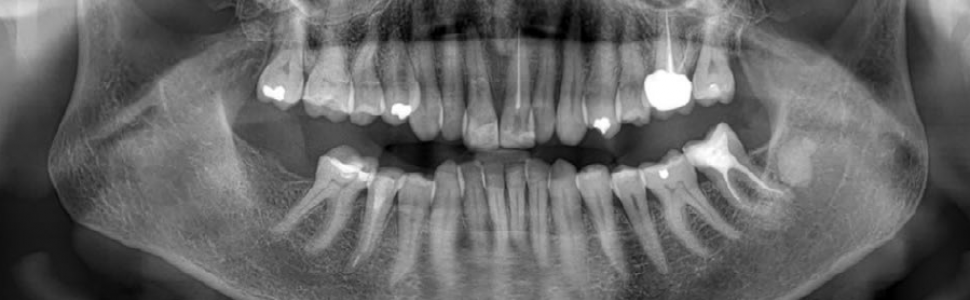

W opisywanym przypadku 60-letnia pacjentka zgłosiła się z powodu urazu komunikacyjnego, w wyniku którego doszło do poddziąsłowego pionowego złamania korony i korzenia zęba siecznego przyśrodkowego szczęki po stronie prawej. Po ostrożnym usunięciu ruchomego fragmentu zęba 11 oraz oczyszczeniu pola zabiegowego pęknięta część korony w kształcie łuski została połączona z główną częścią korony zęba za pomocą cementu adhezyjnego typu dual-cure (Gradia Core, GC, Tokio, Japonia), a pozostały ubytek tkanek odbudowano z użyciem kompozytu (TetricFlow, Filtek Ultimate, Ivoclar Vivadent, Szwajcaria). Roczna kontrola kliniczna wykazała brak objawów zapalenia miazgi i tkanek okołowierzchołkowych oraz zachowaną żywotność zęba 11, potwierdzoną testem termicznym i elektrycznym.

The female patient in her 60s presented with a 5mm subgingival vertical crown-root split of the tooth 11, which did not expose the pulp, among other injuries sustained from trauma during communication.

Tooth 11 presented only signs of the traumatic event, and after careful movable part removal, cleansing of the operation site, the shell-like part was intraorally connected to the main part of the teeth with dual-cure adhesive resin cement (Gradia Core, GC Tokyo, Japan), with later composite final restoration of the crown. One-year follow-up showed no signs of inflammation and pulp vitality of the tooth 11.